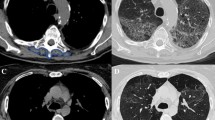

An overall number of 200 patients underwent a HRCT prior to the transplant. Nevertheless, only ninety-seven matched the inclusion criteria and were examined since 75 HRCT did not satisfy the technical criteria while 28 scans were performed earlier than two months before the transplant. The main characteristics of the examined population are summarized in Table 1. The investigated population was composed of 29 women (29.9%) and 68 men (70.1%) and the mean age was 50.4 years old. Most of the patients underwent bilateral lung transplant for idiopathic pulmonary fibrosis (n = 37, 38.1%), followed by cystic fibrosis (n = 12, 12.4%) (Table 1). Overall, 21 (21.6%) patients showed allograft rejection (i.e., fifteen acute and six chronic; Figs. 2, 3).

Forty-year-old female transplanted for cystic fibrosis who developed acute cellular allograft rejection six months after the transplant. In A the coronal reconstruction of the high resolution computed tomography performed before the bilateral lung transplant well demonstrating the severe bronchiectasis affecting the entire left lung as well as the bronchiectasis and ground-glass opacities in the right lung. In B an axial high resoution computed tomography image demonstrating ground-glass opacities and interlobular thickening in the left lower lobe suggesting acute allograft rejection then confirmed by laboratory and histological findings. The patient died a few weeks after the transplant

Twenty-four-year-old female transplanted for, histologically proven, lymphocytic interstitial pneumonia who developed restrictive chronic allograft rejection 20 months after the transplant. In A an axial image of the high-resolution computed tomography performed before the bilateral lung transplant well demonstrating bilateral severe interstitial thickening, bronchiectasis, and fibrotic ground-glass as well as cysts in the left lower lobe. In B an axial high-resolution computed tomography image demonstrating peri-hilar consolidations on the right side as well as band atelectasis and ground-glass opacities in the lower lobes; in C an axial image of the expiratory phase showing air trapping in the lower lobes. The diagnosis of restrictive chronic rejection was achieved including respiratory test as well as laboratory and histological findings